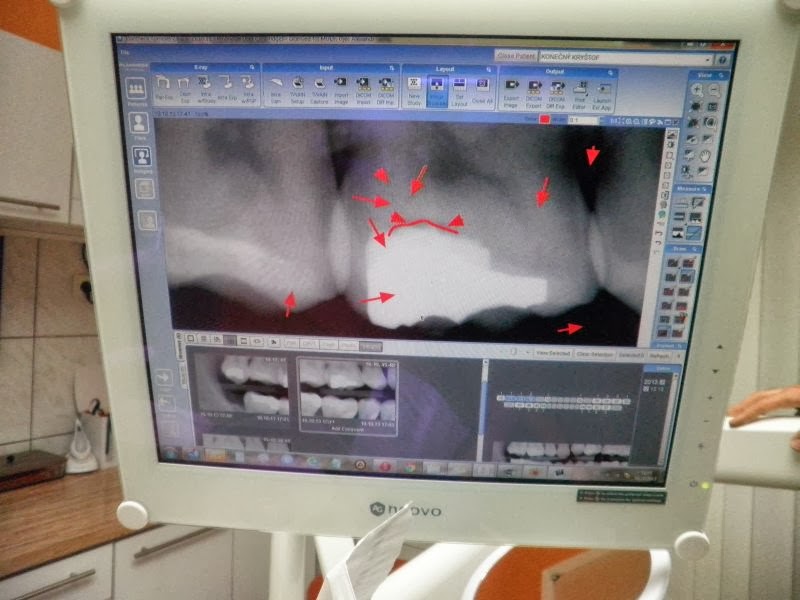

Nejdřív jsem ale přivedla k němu do ordinace Kryštofa, abych viděla, jak pan doktor pracuje in natura a co všechno v ordinaci má a umí. Tohle jsou nejkrásnější chvilky scenáristické práce – sběr materiálu a blbnutí lidí, aby s vámi chtěli spolupracovat. Úspěšnost je překvapivě poměrně vysoká.